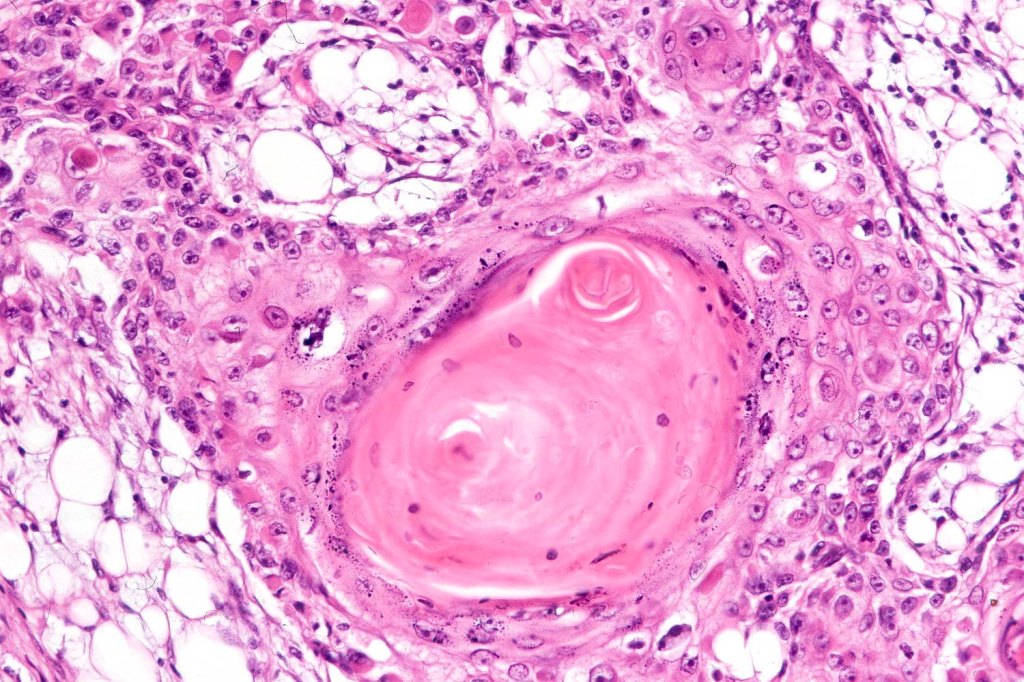

. Presence of desmosomes, individual cell keratinization, keratin pearls, keratocysts

•Varying degrees of squamous differentiation- well, moderate, poorly, undifferentiated & anaplastic